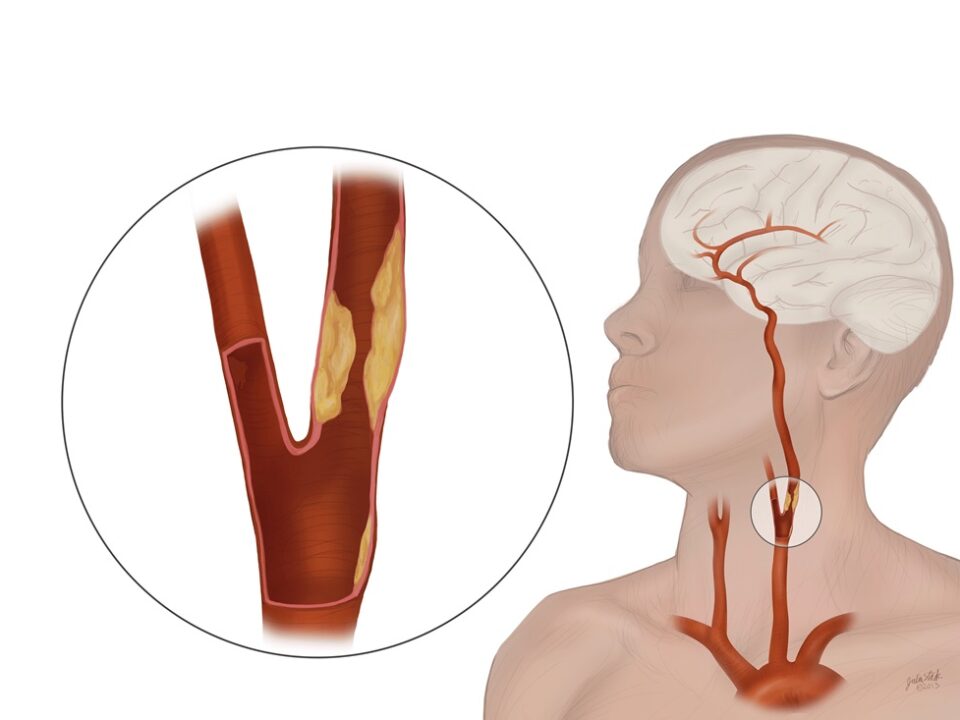

آنژیوگرافی نخاعی: برای تومورهایی که خونرسانی بالایی دارند (مانند همانژیوبلاستوماها)، از این روش برای بررسی عروق تغذیهکننده تومور پیش از جراحی استفاده میشود.